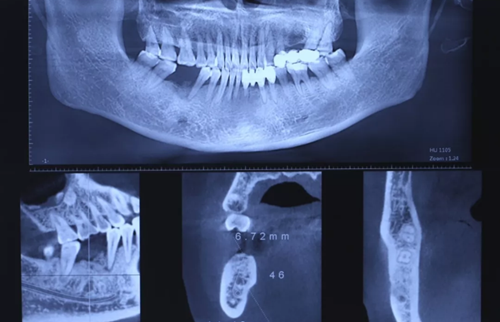

3、術(shù)前全景片

46牙烤瓷冠修復(fù),根折伴大范圍骨吸收。(攝于2016年8月31日)

4、術(shù)前根尖片

10、CBCT檢查

CBCT檢查測量缺牙區(qū)可用骨高度14.40mm,骨寬度6.72mm。

(攝于2017年2月15日)